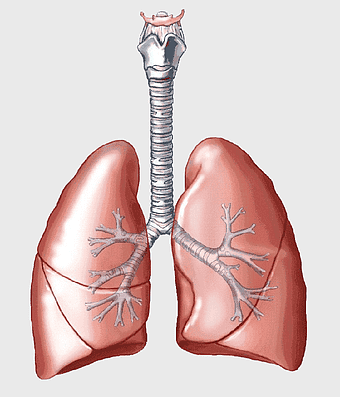

lungs illustration, respiratory system diagram, human lungs anatomy, pulmonary alveolus structure, bronchial tree visualization, trachea and bronchi, lung lobes detail -

Lung Respiratory system, trachea and bronchus, pink lungs illustration, breathing anatomy, pulmonary health, respiratory function, medical education visuals